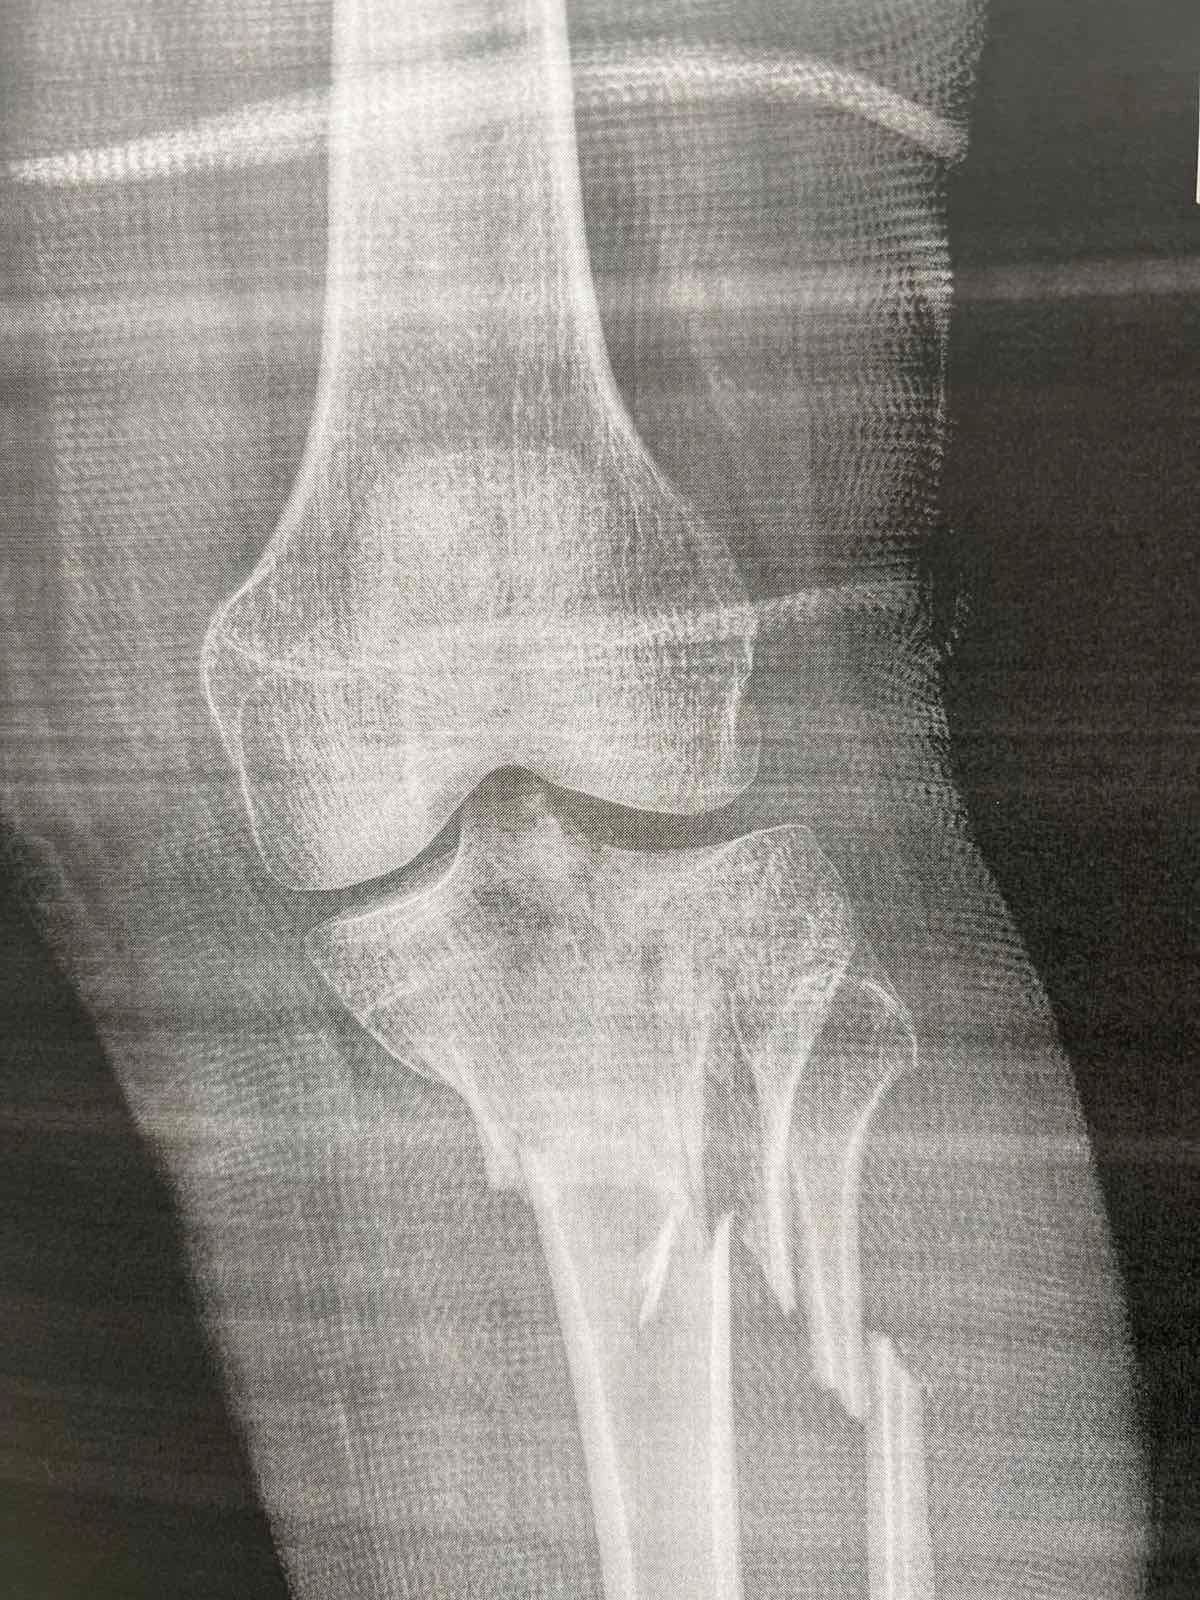

Πριν το χειρουργείο (απεικονίσεις τραυματισμού)

Τα κατάγματα του κνημιαίου πλατώ αφορούν την άνω επιφάνεια της κνήμης που συμμετέχει στην άρθρωση του γόνατος. Η ταξινόμηση Schatzker χρησιμοποιείται ευρέως για να περιγράψει το μοτίβο του κατάγματος.

Ο Schatzker τύπος VI είναι από τις πιο βαριές κακώσεις: πρόκειται για κάταγμα του πλατώ με μεταφυσιο-διαφυσιακή ασυνέχεια(δηλαδή «διαχωρισμό» της μεταφύσεως από τη διάφυση), συχνά μετά από υψηλής ενέργειας τραυματισμό. Τέτοιες κακώσεις μπορεί να συνοδεύονται από σημαντικό οίδημα/βλάβες μαλακών μορίων και απαιτούν ιδιαίτερη προσοχή στον χρόνο και στον τρόπο αποκατάστασης.